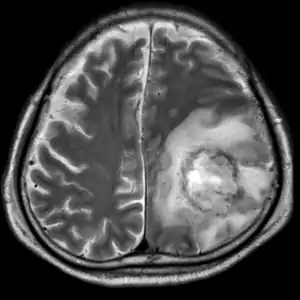

| T2-weighted MRI showing liquefied, necrotic brain tissue as a result of GAE caused by an infection of Acanthamoeba, genotype T18 | |